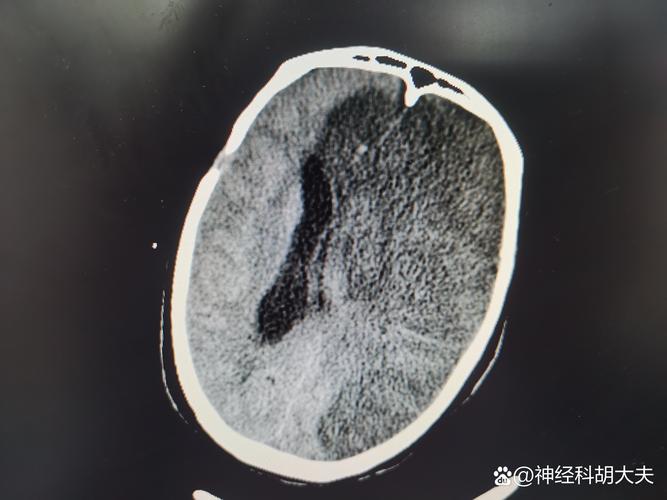

(图片来源网络,侵删)- 单侧的脸部、手臂或腿部突然感到麻木、沉重,像“打了麻药”一样。